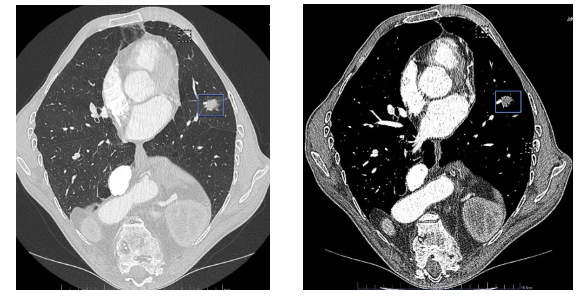

术后首日引流量仅50ml,术后3天复查CT显示左肺复张良好,第4天拔除引流管后出院。“切口藏在乳晕几乎看不到,疼痛轻微,没想到这么大的手术恢复这么快!”对于家人的快速恢复,患者家属十分感激。而这一成果也得益于济宁市第一人民医院推行的ERAS(加速康复外科)理念,通过微创技术、精细化麻醉管理及个性化护理,大幅缩短康复周期。